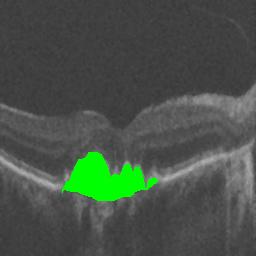

The qualitative results of the proposed system is shown in the Fig. 3. The detection task is evaluated using Area Under the Curve(AUC) metric and the segmentation task is evaluated using Dice Coefficient(DC) metric and the results are presented in Table1

| (a) De-noised OCT slice | (b)Predicted fluid region | (c)Manual fluid segmentation |

| (d) De-noised OCT slice | (e)Predicted fluid region | (f)Manual fluid segmentation |

| (g) De-noised OCT slice | (h)Predicted fluid region | (i)Manual fluid segmentation |

| (j) De-noised OCT slice | (k)Predicted fluid region | (l)Manual fluid segmentation |

| (m) De-noised OCT slice | (n)Predicted fluid region | (o)Manual fluid segmentation |